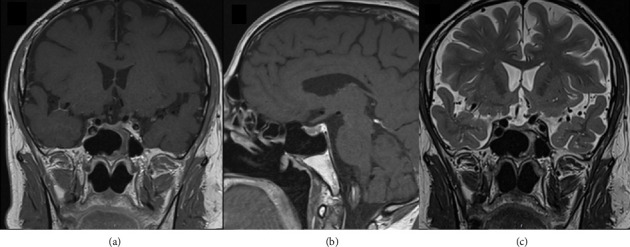

鞍形弓形体病在垂体中的发生极为罕见,文献中仅有少数报道,主要影响免疫功能低下的患者。我们报告一个有趣的情况下,54岁的男子与最初的无症状全垂体功能低下诊断在调查尿石症。头颅CT及MRI显示一大片鞍区病变,初步怀疑为无功能的垂体大腺瘤。经鼻内蝶窦手术,组织病理诊断为垂体刚地弓形虫脓肿。本病例强调,这些类型的感染也可发生在免疫功能正常的患者。

The occurrence of sellar toxoplasmosis in the pituitary gland is exceedingly rare, and only a few reports have been published in the literature, primarily impacting immunocompromised patients. We report an intriguing case of a 54-year-old man with an initial asymptomatic panhypopituitarism diagnosed under investigation for urolithiasis. Cranial CT and MRI revealed a large sellar lesion first suspectable of a nonfunctioning pituitary macroadenoma. An endonasal transsphenoidal surgery was performed, and the histopathological diagnosis was surprisingly a pituitary Toxoplasma gondii abscess. This case highlights that these types of infections can also occur in immunocompetent patients.